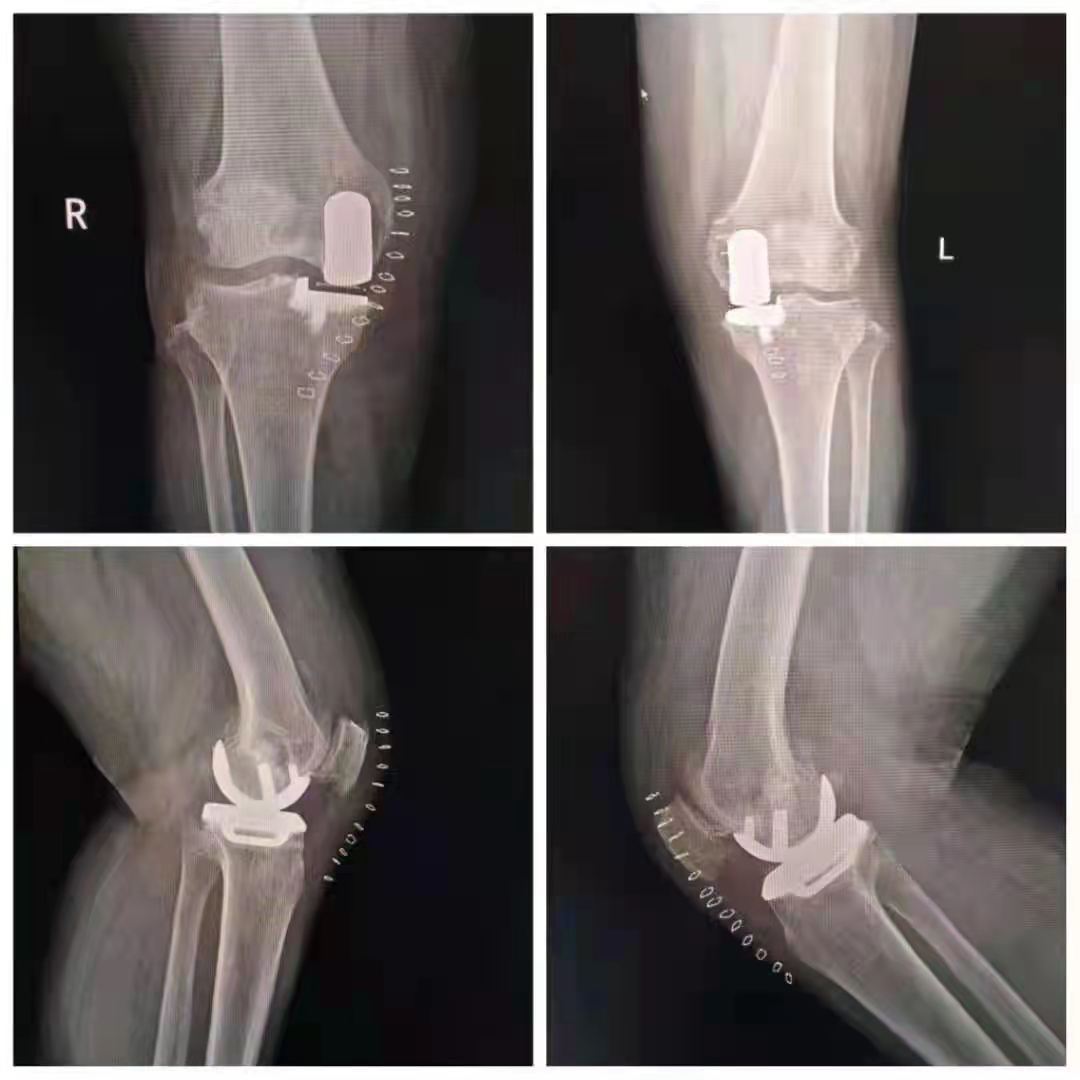

誠德骨科醫(yī)院雙膝單髁置換術(shù)技術(shù)領(lǐng)先

幸運的是,王女士慕名來到了山亭誠德骨科醫(yī)院,專家檢查診斷,發(fā)現(xiàn)王女士雙側(cè)膝關(guān)節(jié)內(nèi)側(cè)磨損嚴(yán)重,外側(cè)部分和前后交叉韌帶上好,因此采取雙側(cè)同期部分置換。應(yīng)用牛津單髁活動平臺,手術(shù)屬于保膝范疇,保留了好的部分,修補(bǔ)了磨損重的部分,病人感受好,恢復(fù)快,功能好。如果錯過這個修補(bǔ)的時機(jī),整個關(guān)節(jié)都磨損了,只能進(jìn)行全膝置換了。

術(shù)后,王女士恢復(fù)很好。疼痛癥狀完全消失,臉上也露出了久違的笑容。